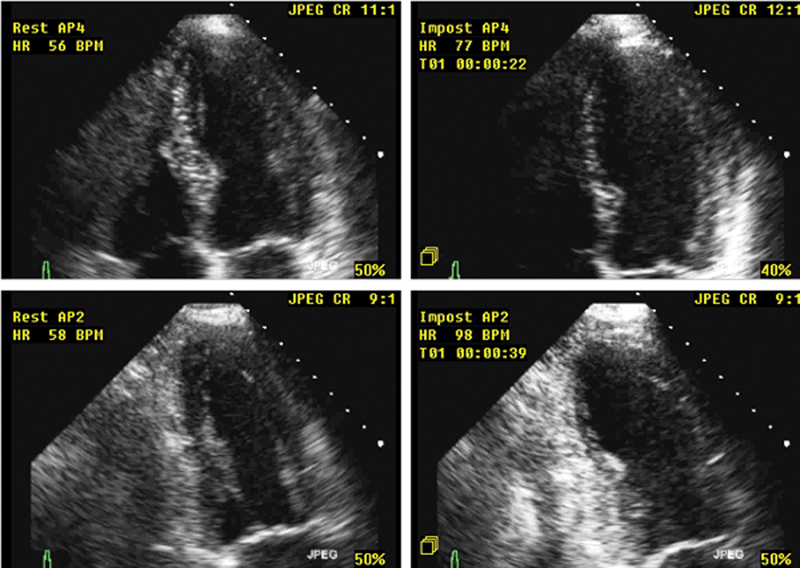

فحوصات تشخيصية لبعض امراض القلب والشرايين التاجية